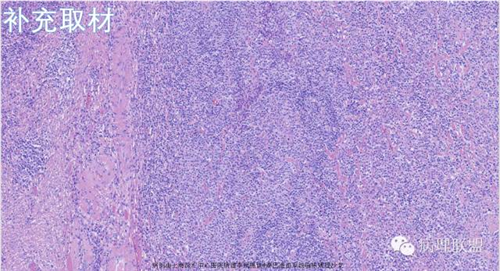

M,79岁,右半结肠粘膜下肿块。大小:6.5*6*6cm球形肿块,切面灰白质硬,界清。第一次取材。